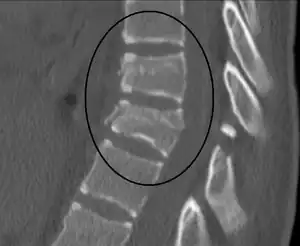

| Chance fracture | George Quentin Chance | horizontal fracture of vertebral body | hyperflexion of spine, seen in car accidents when lap belts were used | Chance fracture Archived 2018-07-06 at the Wayback Machine at Wheeless' Textbook of Orthopaedics online |

| Clay shoveller's fracture | Clay shovellers | spinous process fracture of C6, C7 or T1 | forced hyperflexion of neck | "Clay shovellers fracture". Medcyclopaedia. GE. Archived from the original on 2011-05-26. Retrieved 2023-03-25. | |